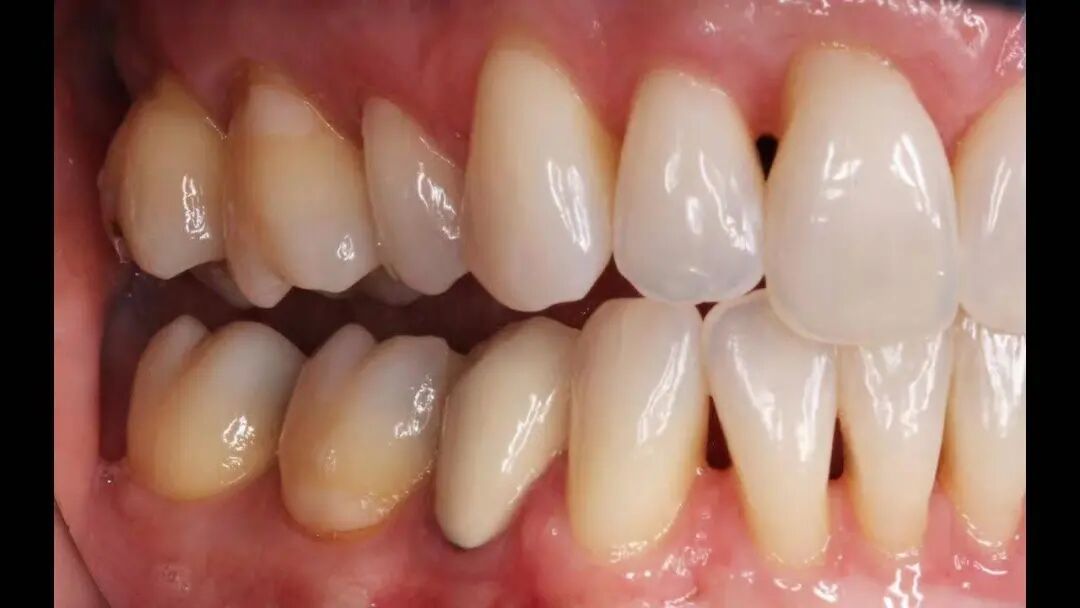

四. 如何判断自己有没有牙周病?